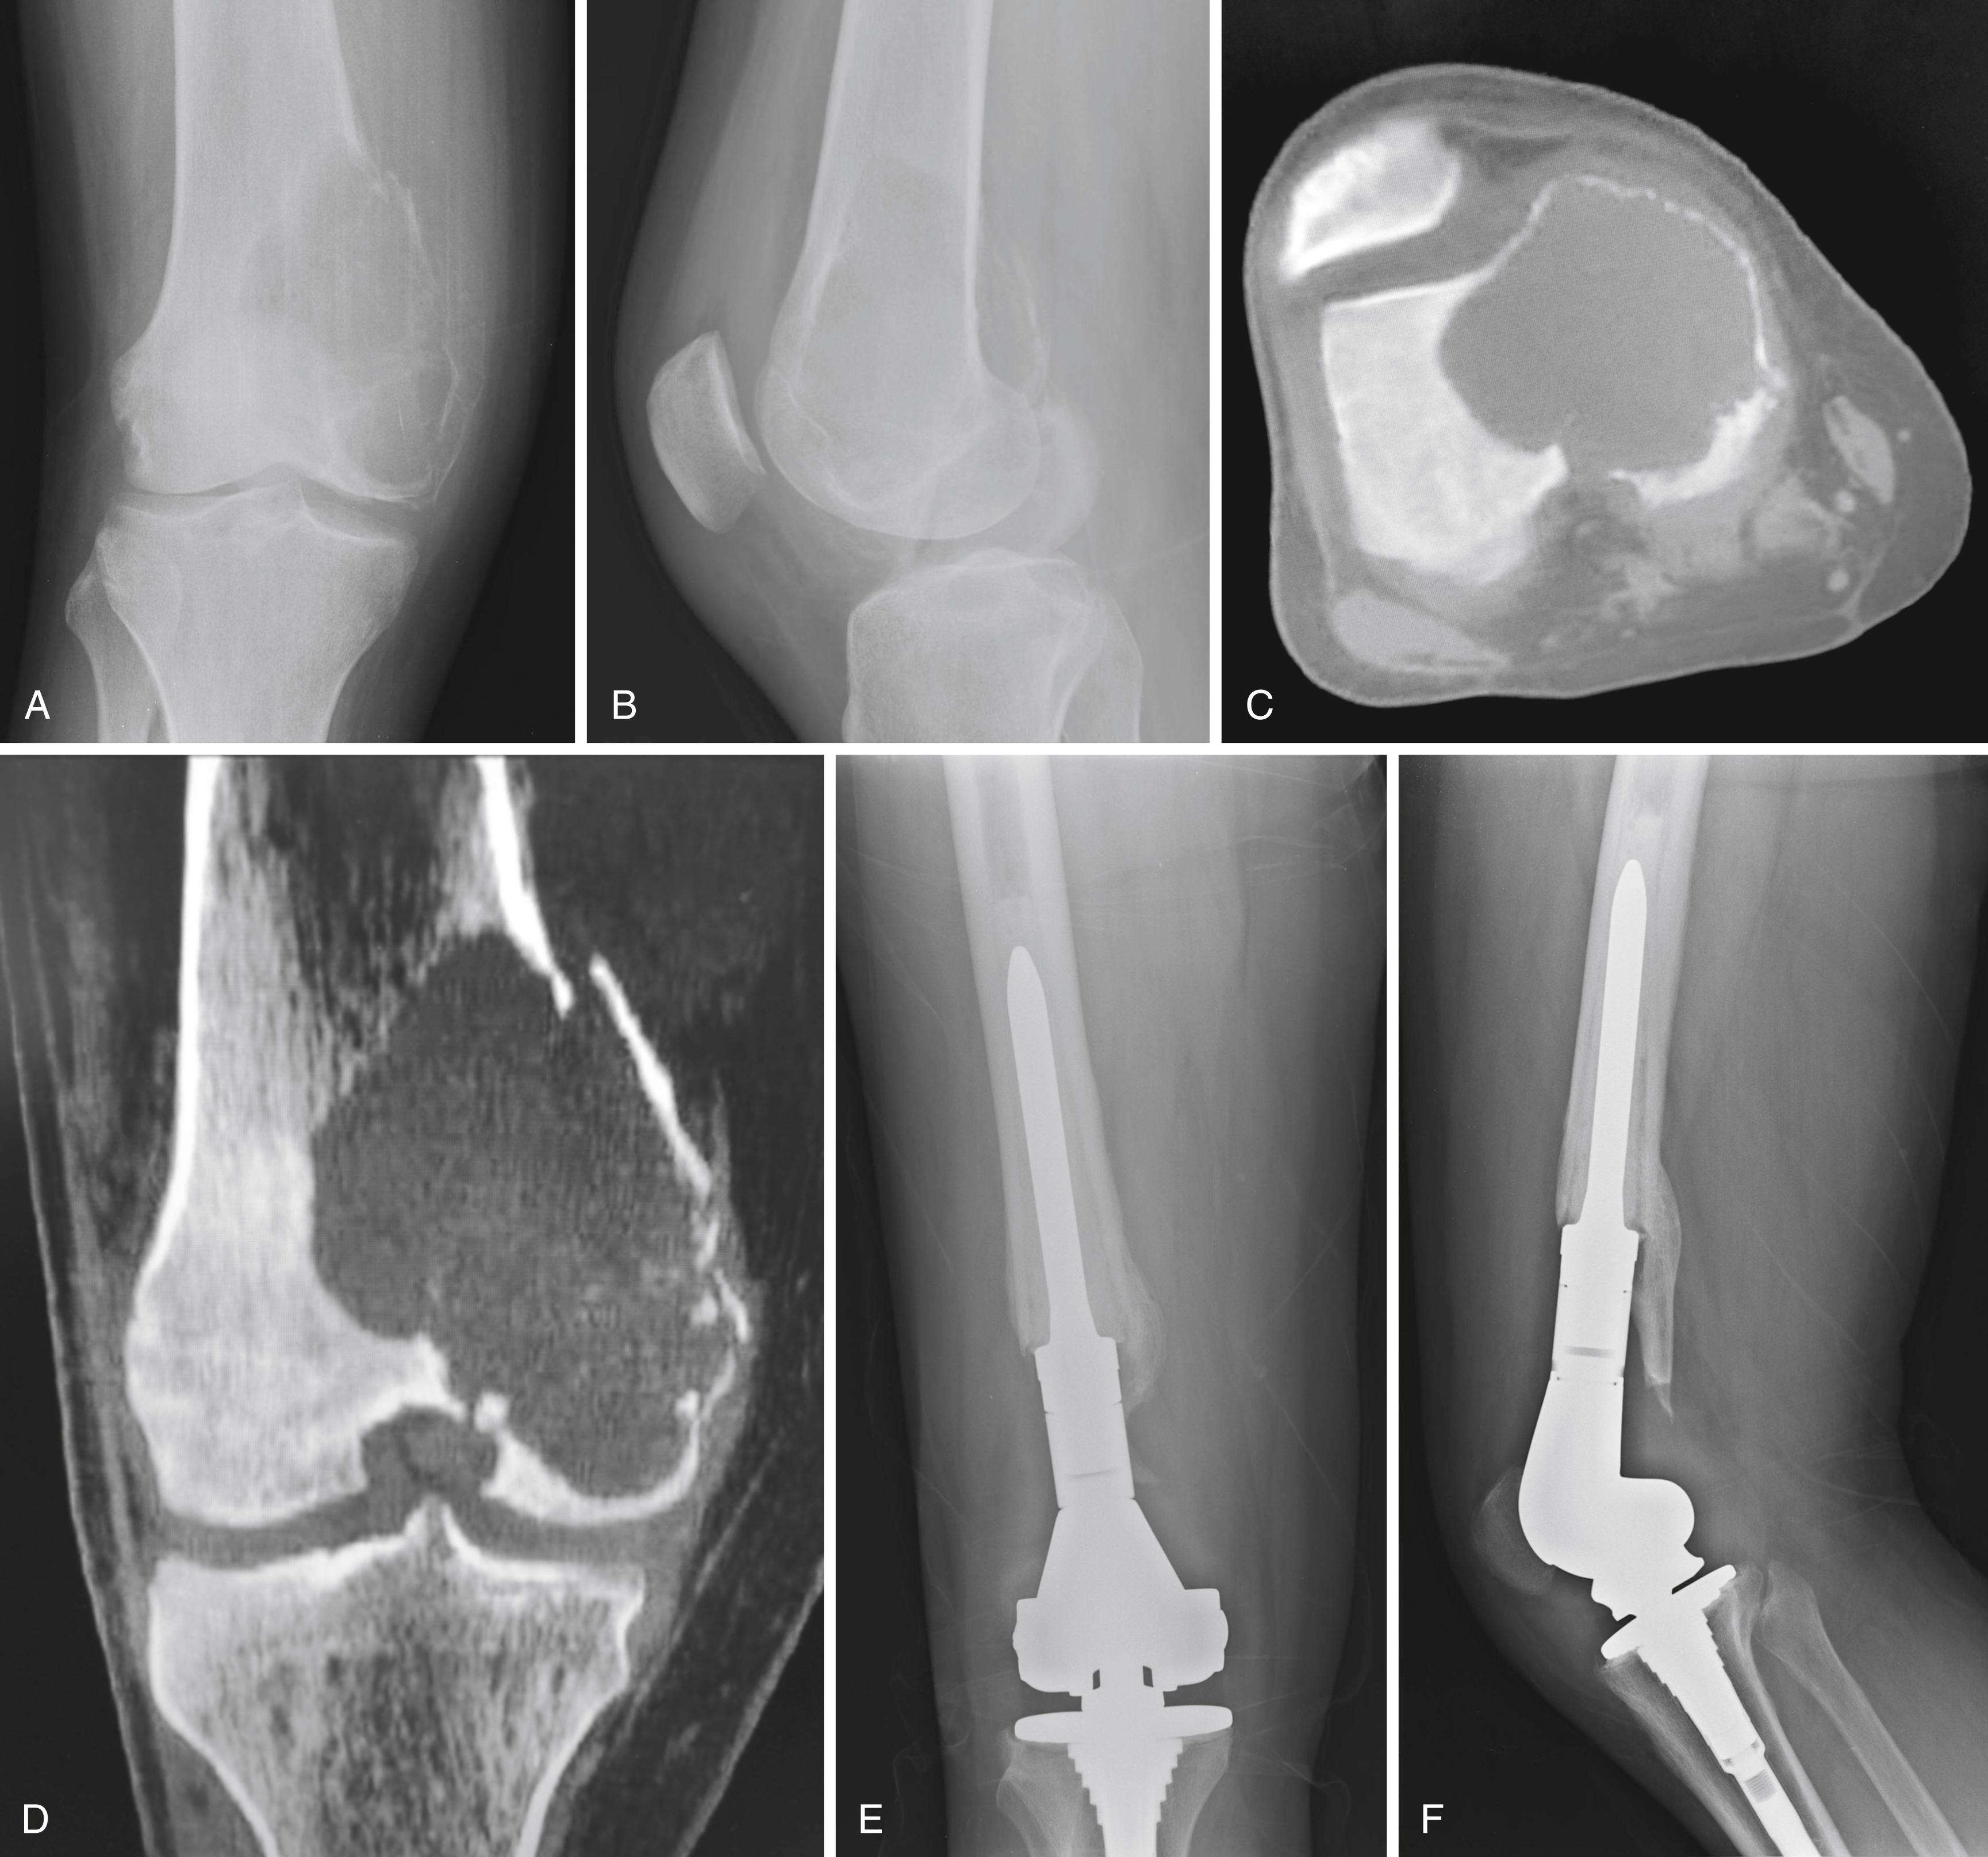

FIGURE 26.3, Anteroposterior (A) and lateral (B) radiographs of a 28-year-old man with a giant cell tumor of the right distal femur. Axial (C) and coronal (D) CT reconstructions demonstrate extensive bone destruction and an intraarticular pathologic fracture. The decision was made to proceed with en bloc resection and endoprosthetic reconstruction. Anteroposterior (E) and lateral (F) postoperative radiographs. Patient currently is doing well 8 years after surgery.